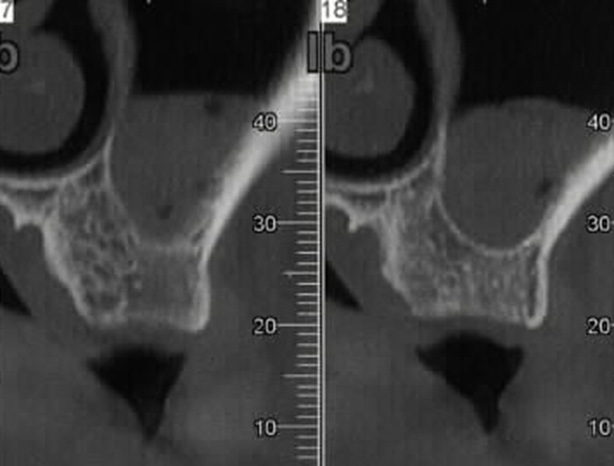

Various implant neck designs and surface modifications have been proposed to minimize CBL. Among these, a platform switch associated with laser-ablated microchannels placed within the implant collar has shown favorable results.17 Platform switching involves the use of a prosthetic abutment with a smaller diameter than the implant platform, thereby influencing the peri-implant biological width through geometric modification of the supracrestal connective tissue space. Additionally, laser-microgrooved surfaces have been developed to guide the alignment and the subsequent growth of fibroblasts at the implant neck (Figure 1).18, 19, 20 Histological studies in humans have demonstrated a different organization of peri-implant soft tissues around laser-microgrooved surfaces compared to machined (smooth) surfaces, characterized by an intimate physical contact of connective tissue and perpendicularly oriented collagen fibers along the laser-ablated, microgrooved implant necks.21

Platform switching34 and laser-microgrooved surfaces35 are implant design modifications aimed at reducing CBL. Platform switching involves the use of prosthetic abutments with a smaller diameter than the implant platform at the implant–abutment interface. This configuration results in a geometric manipulation of the supracrestal connective tissue, which thickens horizontally and may help protect the crestal bone from reabsorption. Another method attempting to reduce crestal bone remodeling is the use of a laser-microgrooved coronal surface at the implant neck. Laser-microgrooved surfaces were developed to modify cellular interactions with the titanium surface. These surfaces are created using controlled excimer laser ablation, which allows for the creation of a microgeometry characterized by parallel linear grooves with resolution in the micrometer range (Figure 1). Pre-clinical studies have shown that laser-microgrooved surfaces present a high potential for the growth of fibroblasts and effective inhibition of epithelial cell migration across the grooves.19 In contrast to implants with machined (smooth) necks, which typically exhibit a parallel distribution of collagen fibers, histological analyses have demonstrated that laser-microgrooved surfaces promote a more intimate connective tissue attachment, with fibers oriented perpendicularly to the implant surface.20 This configuration may contribute to improved protection of peri-implant crestal bone remodeling.35, 36, 37